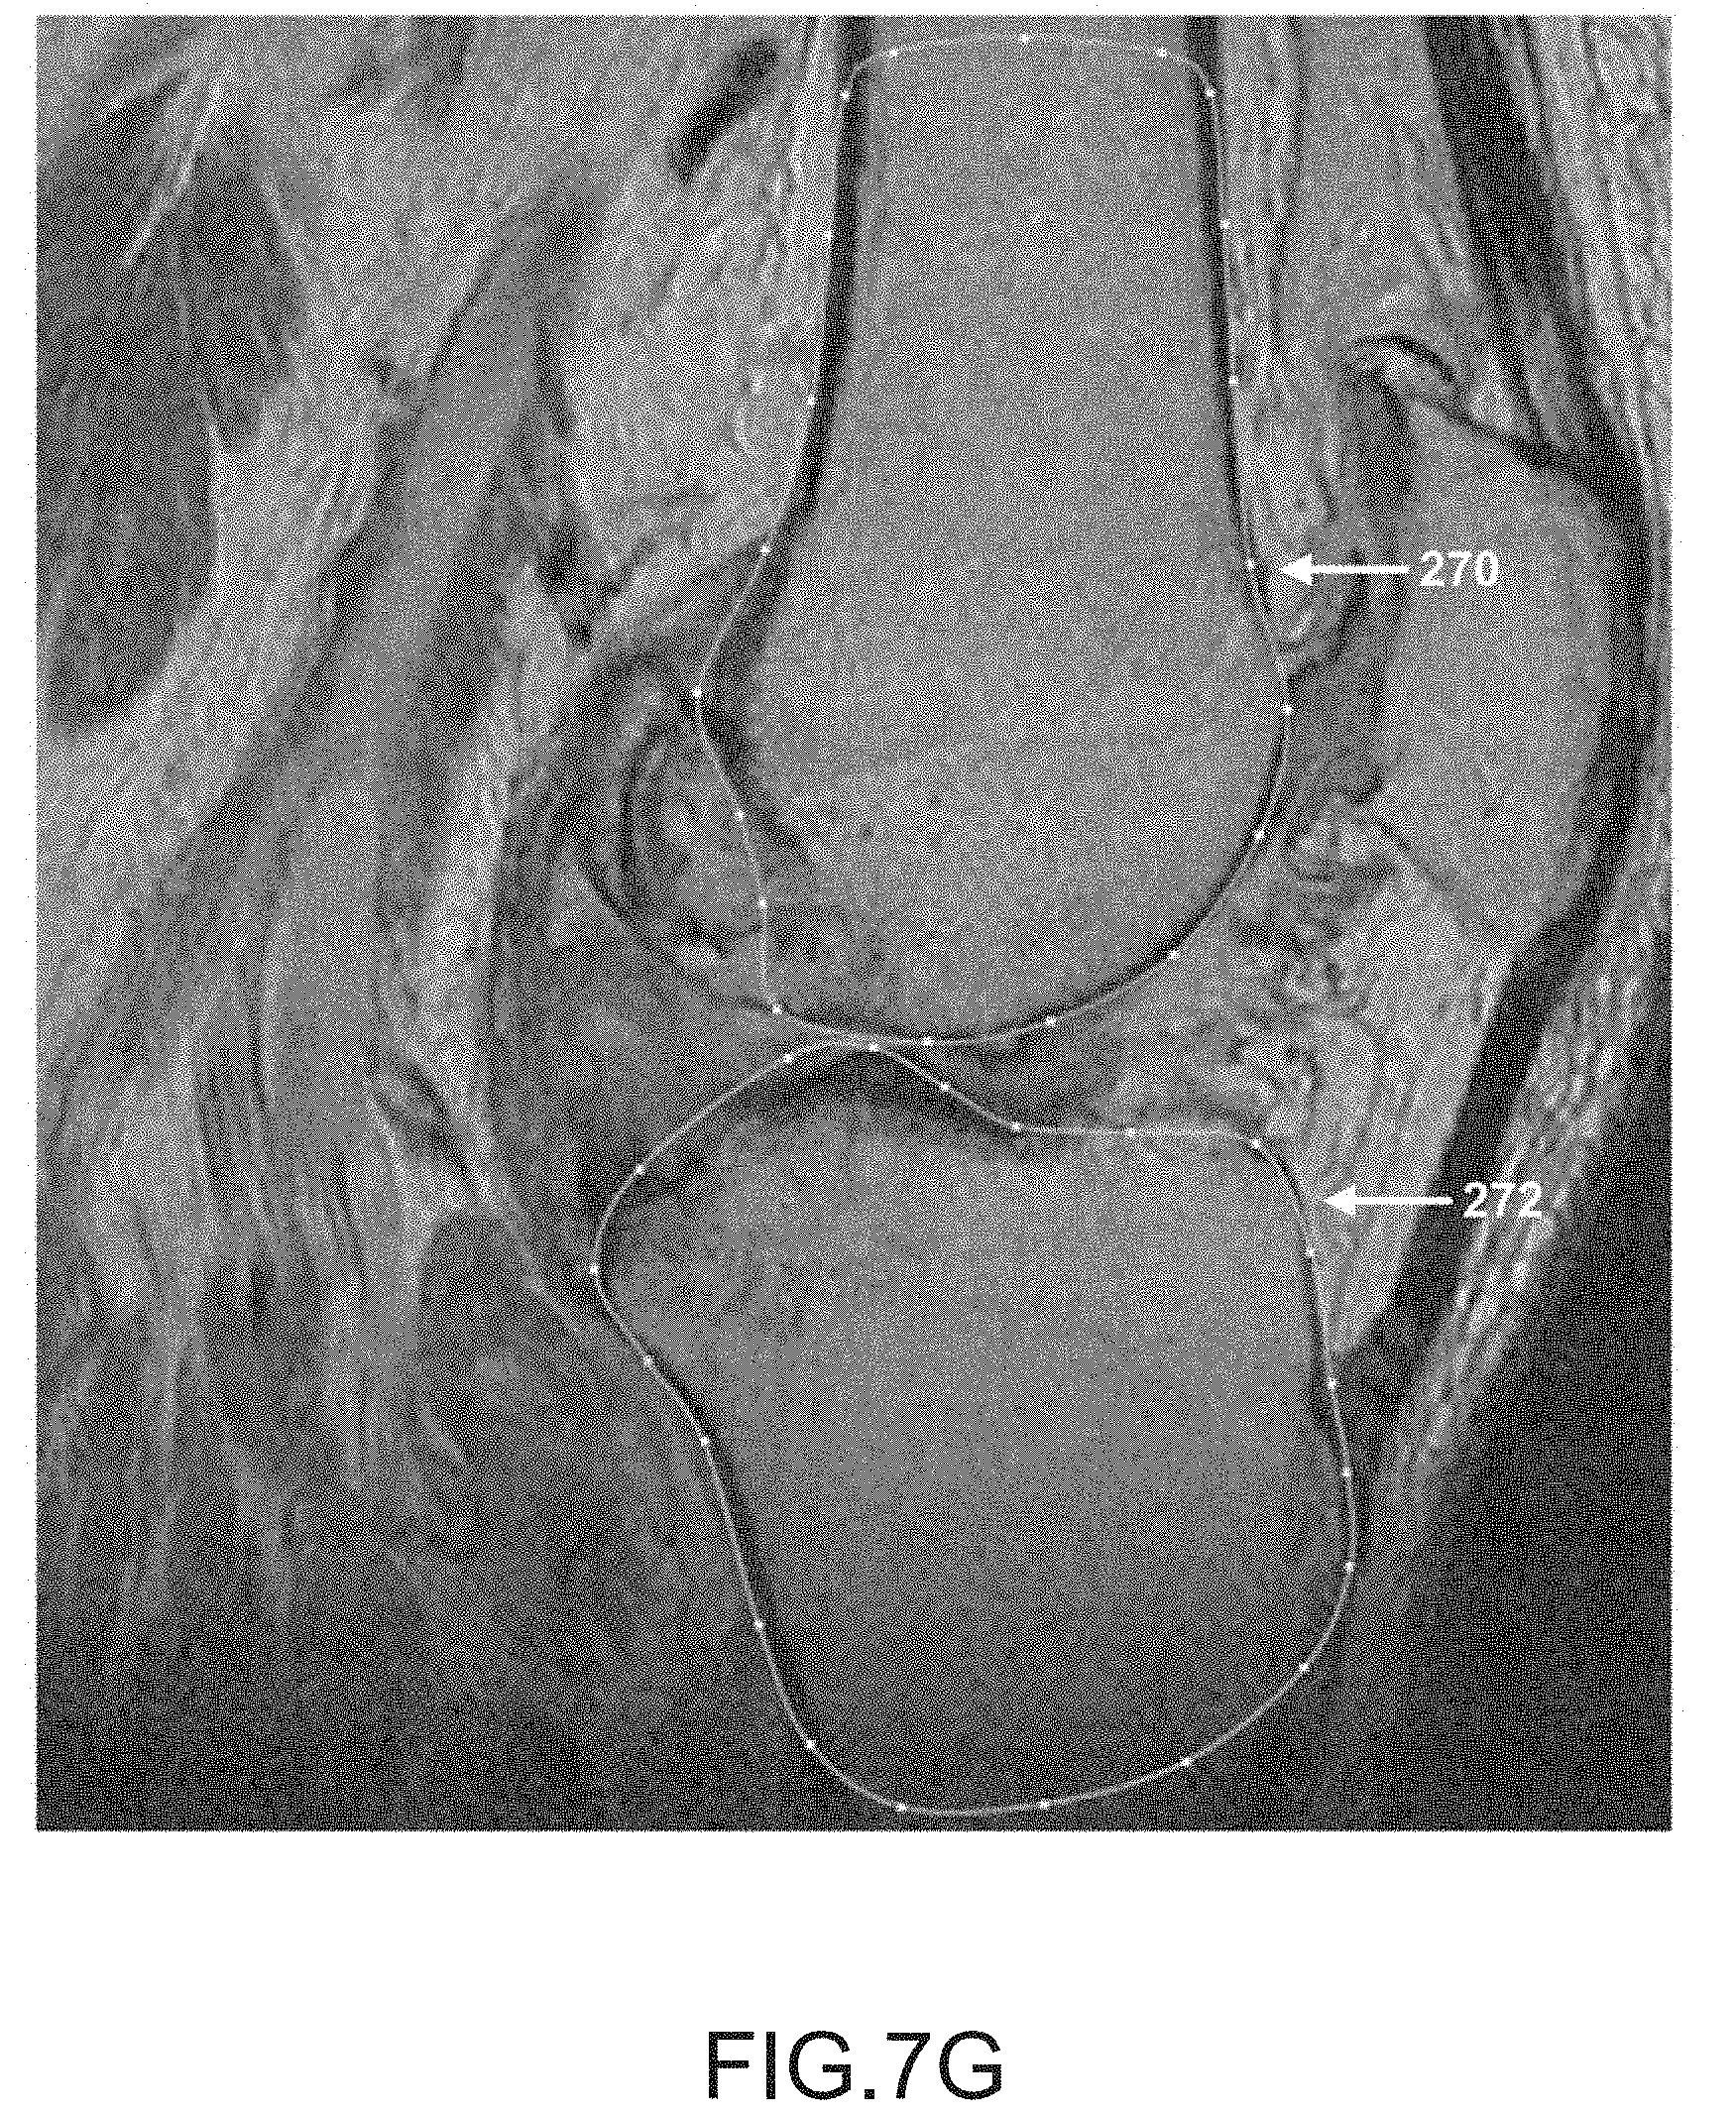

FIG. 7G is another sagittal plane image slice of a segmented femur and tibia.

After operation 250 obtains scan data (e.g., scan images 16) generated by imager 8, operation 252 may be performed to segment the femur data of the scan data. During this operation, the femur may be located and spline curves 270 may be generated to outline the femur shape or contour lines in the scan slices, as depicted in FIGS. 7A-7K. It should be appreciated that one or more spline curves may be generated in each slice to outline the femur contour depending on the shape and curvature of the femur as well as the femur orientation relative to the slice direction.

After operation 256, operation 258 may be performed to segment the tibia data in the scan data. During this operation, the tibia is located and spline curves may be generated to locate and outline the shape of the tibia found in the scan slices, as depicted by tibia spline curves 272 in FIGS. 7A-7K. It should be appreciated that one or more spline curves may be generated in each slice to outline the tibia depending on the shape and curvature of the tibia as well as the tibia orientation relative to the slice direction.